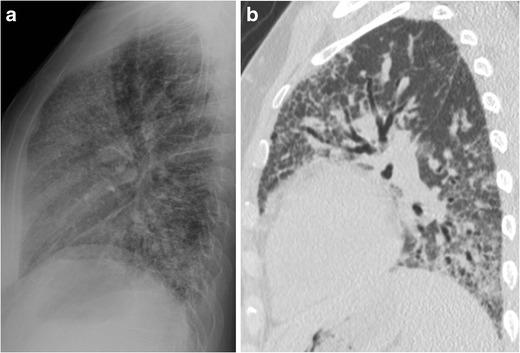

The retrosternal clear space (RCS) is a lucent area on the lateral chest radiograph located directly behind the sternum. The two types of pathology classically addressed in the RCS are anterior mediastinal masses and emphysema. Diseases of the pulmonary interstitium are a third type of pathology that can be seen in the RCS. Retrosternal reticular opacities, known as Kerley D lines, were initially described in the setting of interstitial oedema. Pulmonary fibrosis is another aetiology of Kerley D lines, which may be more easily identified in the RCS than elsewhere on the chest radiograph.

• The RCS is one of three lucent spaces on the lateral chest radiograph. • Reticular opacities in the RCS are known as Kerley D lines. • Pulmonary fibrosis can be seen in the RCS as Kerley D lines. • Kerley D lines should be further evaluated with chest CT.

胸骨后透亮区(RCS)是胸部侧位X线片上位于胸骨正后方的透亮区域。RCS中经典提及的两种病理类型是前纵隔肿块和肺气肿。肺间质疾病是可在RCS中见到的第三种病理类型。胸骨后网状模糊影,即克氏D线,最初是在间质性水肿的情况下描述的。肺纤维化是克氏D线的另一种病因,在胸部X线片上,其在RCS中可能比其他部位更容易识别。

• RCS是胸部侧位X线片上的三个透亮区之一。• RCS中的网状模糊影称为克氏D线。• 肺纤维化在RCS中可表现为克氏D线。• 克氏D线应进一步行胸部CT评估。